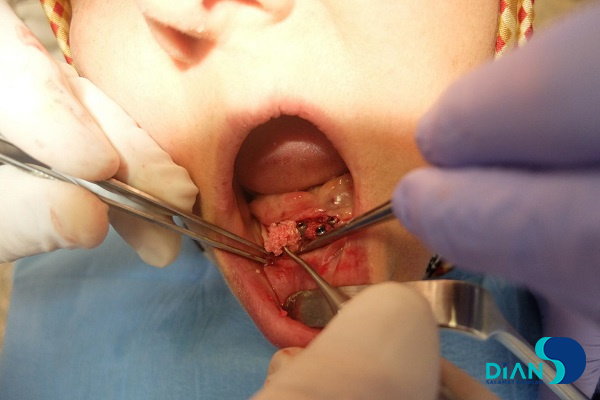

A patient with fully edentulous upper jaw and bridgework on the lower jaw came to dental clinic seeking for dentition restoration. After examination, the dentist decided to extract bridgework and to place implants from Bio3 in teeth sockets. After bridgework extraction, the dentists started to form implant beds. Then he placed implants from Bio3 Implants. Next stage was to place PRF-clot and bone tissue material into the wound and suture it. In first part of this clinical case we saw placement of dental rehabilitation using implants by Bio3. In this part you can find the result of first implantation with bone augmentation and additional placement of implants by Bio3. This case report was presented by Dr. Saniye Tümay (Turkey).